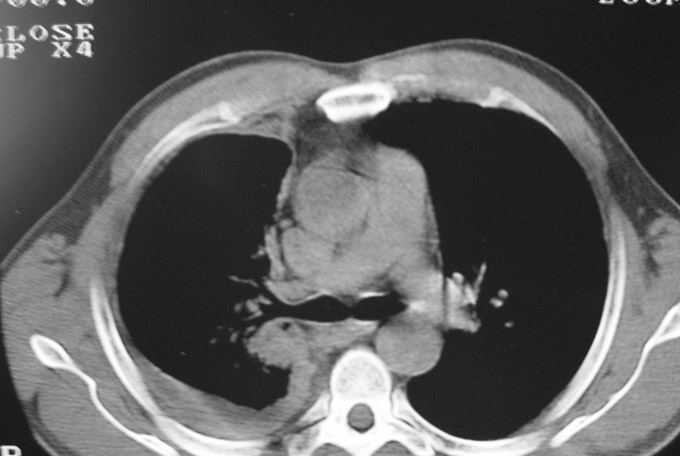

以下是引用守望可可西里在2006-9-11 15:29:00的发言:[br][br] ct平扫表现:右侧胸膜腔缩小,积液,胸膜增厚且不均匀、不规则,以纵隔胸膜增厚为主,边缘呈锯齿状,并见附壁内突之结节状肿块影。右肺含气量减少,纹理聚集,右肺门中下部见数个肿大的淋巴结。纵隔无移位,内未见明显肿大淋巴结,双侧主支气管以及各叶、段支气管比较通畅。。[br] 考虑:右侧胸膜恶性间皮瘤,伴肺门淋巴结转移。